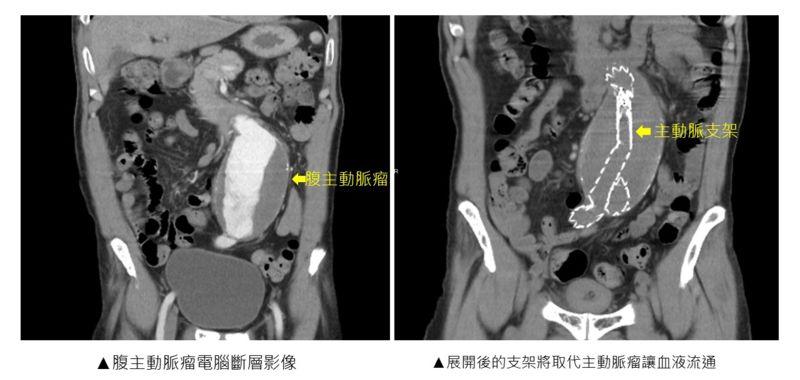

國軍臺中總醫院心臟血管外科自2017年起,引進了微創主動脈血管內支架手術,造福許多可能需要進行傳統開放式手術的高風險主動脈瘤病患。微創主動脈支架手術是先在腹股溝切開兩道傷口,將導管插入股動脈,接下來輸送主動脈支架到主動脈瘤的位置並展開主動脈支架,展開後的支架將取代主動脈瘤讓血液流通,因此主動脈瘤不會再受血流衝擊,導管自主動脈移除後,將股動脈縫合修補,始才完成手術;而傳統開放式手術則是需要切開腹部一道大約20至30厘米的開口,以利進行主動脈瘤的切除,以及縫合置換上人工血管。

為蔡先生進行微創主動脈血管內支架手術的林敬惟醫師,於本次手術進一步搭配使用經皮血管縫合器系統,利用穿刺的方式取代用手術刀切開傷口,讓兩側腹股溝的傷口從5至7厘米大小縮小至1厘米不到!如此超微創的傷口讓蔡先生術後幾乎感覺不到疼痛,覺得非常驚奇,術後恢復也十分迅速。